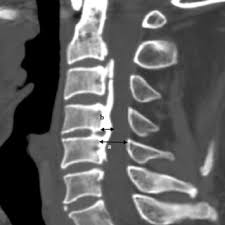

Sagittal Canal Occupying Ratio:

·   Obtain a midsagittal CT image of the cervical spine through the center of the spinal canal with clear visualization of the OPLL

·   Identify the midsagittal slice at the level of the maximum OPLL thickness (the point where the ossification protrudes most posteriorly into the canal)

·   Measure the sagittal anteroposterior (AP) diameter of the spinal canal (diameter “D”) at the level of the maximum OPLL, from the posterior cortex of the vertebral body to the anterior cortex of the lamina (or spinolaminar line)

·   Measure the maximum sagittal AP thickness of the OPLL (diameter “d”) at the same level, from the posterior cortex of the vertebral body to the most posterior margin of the ossification

·   Calculate the Sagittal COR: Sagittal COR (%) = (d / D) × 100